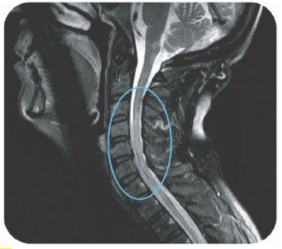

Area postrema syndrome is a core clinical characteristic of NMOSD that can appear both at disease onset and throughout the clinical course7

- The spectrum of NMOSD symptoms is broad and includes nausea, vomiting, and intractable hiccups7,8

- 4 out of 10 NMOSD attacks of the area postrema include all 3 symptoms7

- Due to symptom severity, ~80% of patients with NMOSD-related area postrema syndrome are hospitalized7